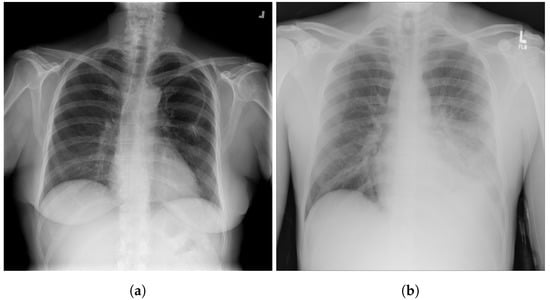

3.7. Shenzhen Hospital X-ray

3.8. National Institute of Health (NIH)